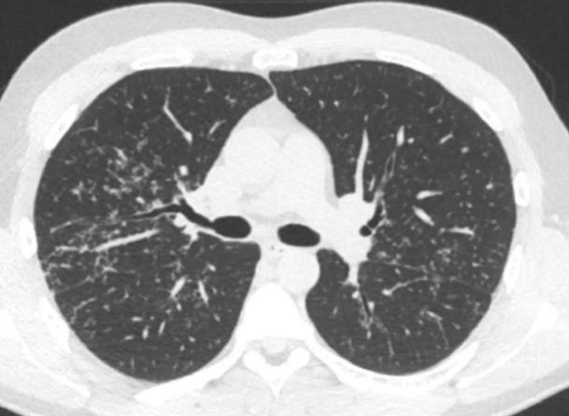

DT lunga

Vad visar bilden?

Små nodulära förändringar, kring pleuran, men också runt kärl liksom mellan lober, mellan bronker typiskt vid sarkoidos, även amyloidos som differentialdiagnos, liksom tuberkulos.

Björn Lundberg, 38 år med yrsel, hjärtklappning och ibland svimning. Telemetri på avdelningen visar frekventa VES samt längre och korta VT med olika fokus. I samband med episoder av längre VT har Björn yrsel. Biokemiskt noteras mindre läckage av Troponin T utan dynamik. Akut ekokardiografi visar lätt nedsatt vänsterkammarfunktion samt hypo-/akinesi inferiort. MR visar kontrastuträde subepikardiellt i inferiora delar hjärtat.

Beslut fattas att lägga ICD pga. oro för framtida malign arytmi (VT/VF). Pat har inga klagomål utöver yrsel. Framkommer dock rethosta sedan drygt 6 månader

Patienten har flera gånger blivit uppmanad av hustrun att söka för hostan

Lungröntgen visar

Spirometri visar inga avvikelser